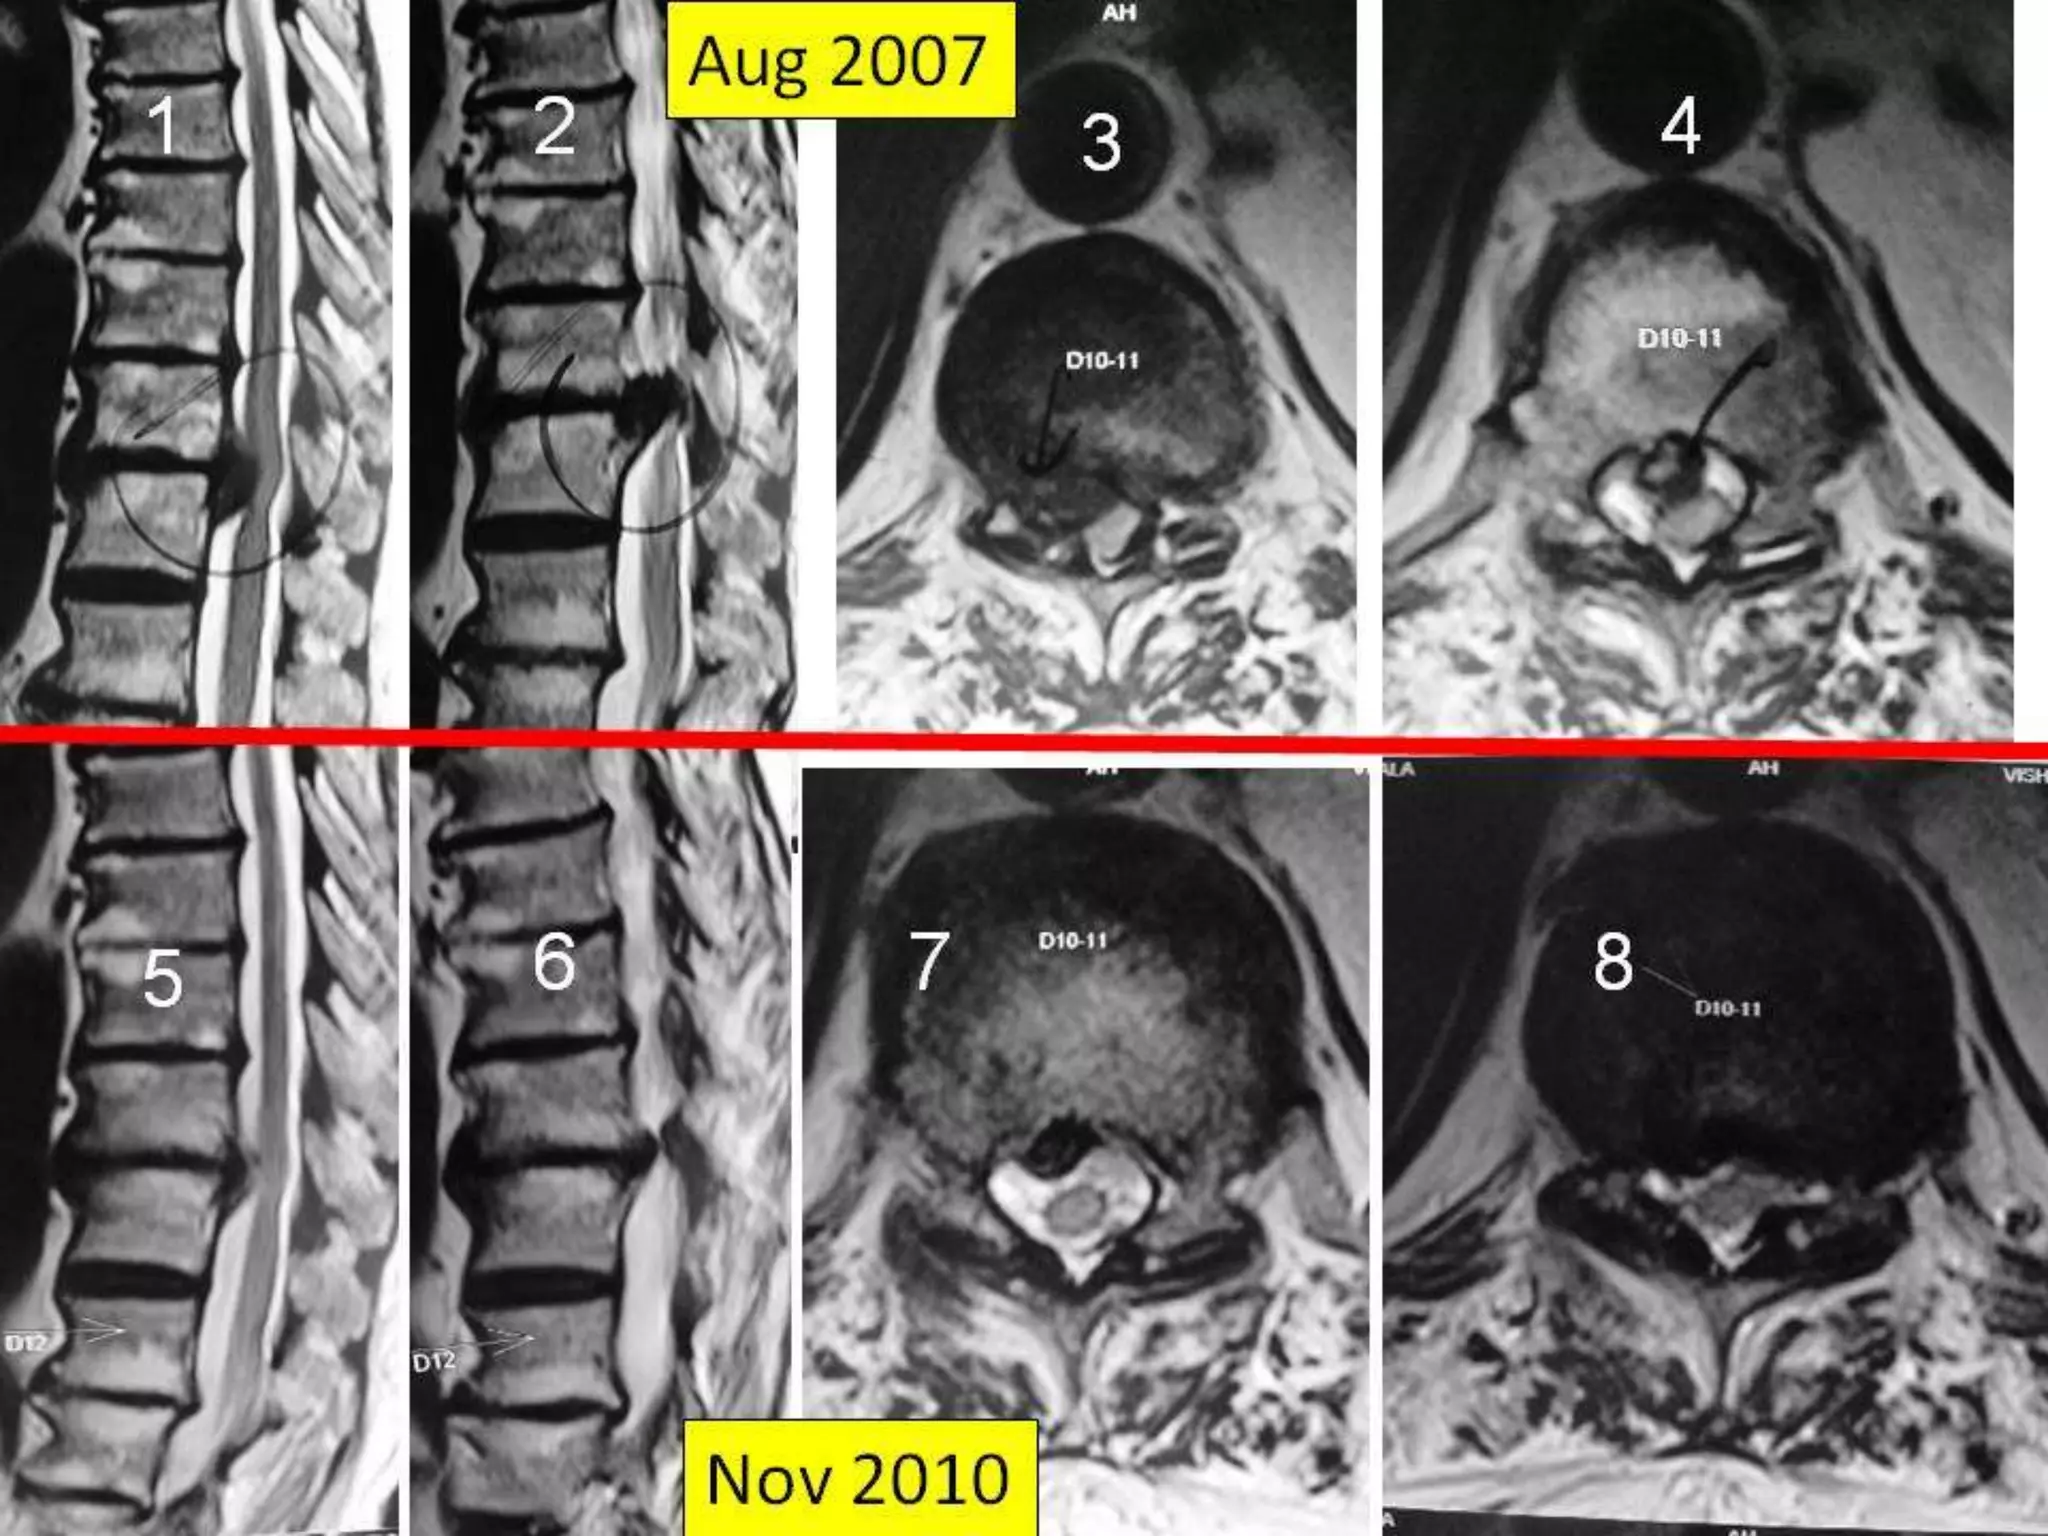

Dorsal Discs

Disc at D12 – L1

Post operative Right sided Facetactomy